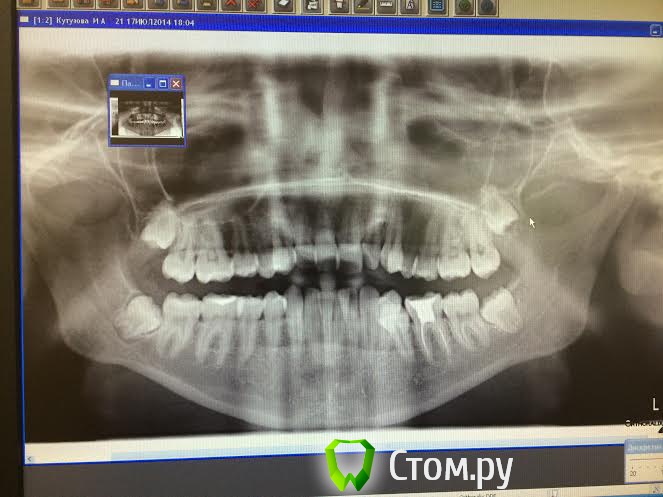

nadya1 Опубликовано 4 августа, 2014 Поделиться Опубликовано 4 августа, 2014 Добрый день коллеги, прошу Вашего совета, есть пациентка, которая в силу своей занятость и нечастого нахождения в СПб хочет одномоментно убрать 4!!!! восьмерки снимок в приложении, с каких зубов лучше начинать верхних или нижних Я сама думаю с верхних 18; 28, потом 38 и закончить 48 с выпиливанием и ушиванием. очень боюсь остеомиелита у девушки есть аллергия на лекарства... Ссылка на комментарий

CToMaToJlor Опубликовано 5 августа, 2014 Поделиться Опубликовано 5 августа, 2014 По снимку самым проблематичным выглядит 28. И сложность его удаления будет определяться доступом( толшиной щек, открыванием рта, методами работы анестезиолога) Ссылка на комментарий